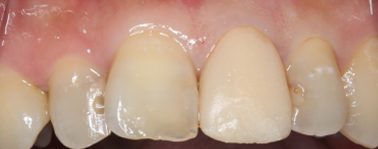

連結してあった前歯の被せ物(歯茎まで黒くなっている)も矯正後にきれいに治療することが出来ています。

処置後、非常に審美的な補綴物が入ったことが分かるかと思います。

非常に審美的な治療が出来ました。

当院では難しい前歯のインプラントも違和感なくきれいに処置することが出来ます。